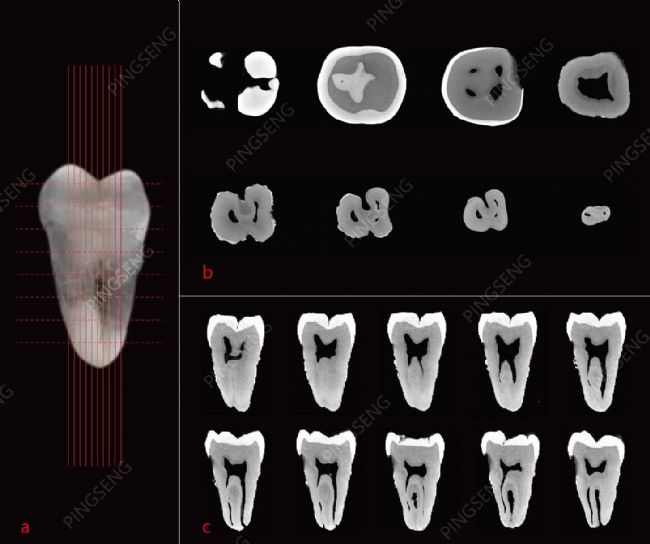

圖1 平生Avatar軟件可對牙齒的牙釉質(zhì)、牙本質(zhì)和牙髓腔進行單獨且準(zhǔn)確的分割,并提供精準(zhǔn)的定量分析和可視化。

圖4:Avatar軟件還可以生成連續(xù)的切片,準(zhǔn)確可靠地顯示牙釉質(zhì),牙本質(zhì)和牙髓腔的厚度和面積。 (a.成人的真牙照片,灰度色調(diào)處理;b.橫向切片展示;c.縱向切片展示)